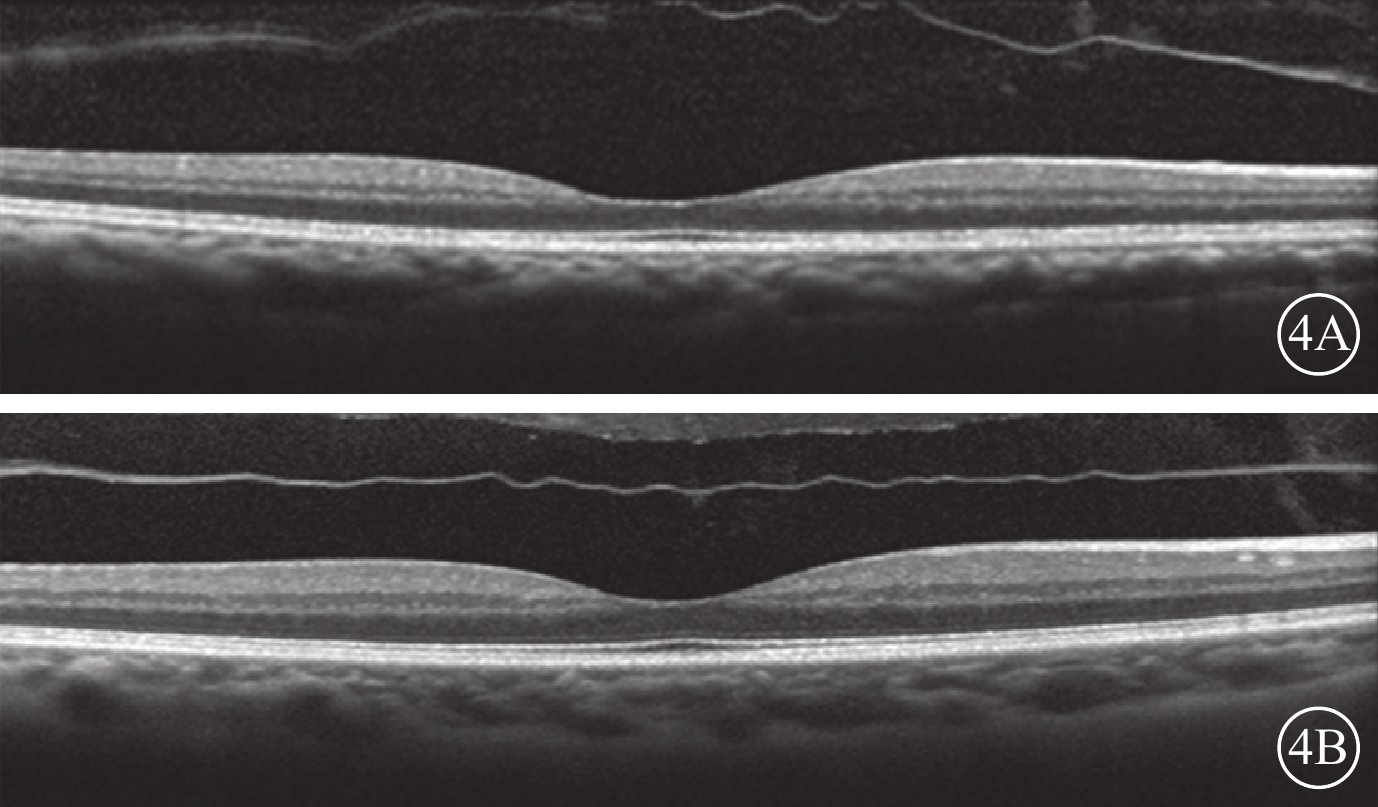

圖2

VMI異常的對照眼OCT像。2A. 黃斑中心凹區域局灶型VMA(白箭);2B. 黃斑區廣泛型VMA(白箭)

圖2

VMI異常的對照眼OCT像。2A. 黃斑中心凹區域局灶型VMA(白箭);2B. 黃斑區廣泛型VMA(白箭)

所有患者均采用3+PRN的方式接受玻璃體腔注射抗VEGF藥物治療。治療前采用OCT觀察患者雙眼的VMI情況。以中心凹為中心,掃描黃斑區,使用高速模式。(1)體積掃描:ART疊加次數9次,97線掃描線,20°×20°;(2)十字掃描:ART疊加次數36次,2線掃描線,20°×20°。將存在玻璃體黃斑粘連(VMA)、黃斑前膜(MEM)、完全性玻璃體后脫離(C-PVD)定義為VMI異常。以玻璃體粘附在中心凹中心3 mm直徑內,但部分玻璃體視網膜分離為VMA;并根據OCT圖像上玻璃體與黃斑部粘附的直徑大小將VMA分為局灶型(≤1500 μm)和廣泛型(>1500 μm)[17]。以鄰近或貼覆在黃斑前、較玻璃體后界膜厚且反射性強的組織為MEM[18]。以玻璃體后界膜高起,與視網膜黃斑無粘附為C-PVD[19-21]。34只研究眼中,存在VMI異常(圖1)12只眼。其中,廣泛型VMA 8只眼,局灶型VMA 3只眼,MEM 1只眼;合并存在局灶型VMA、MEM 1只眼。34只對照眼中,存在VMI異常(圖2)12只眼。其中,廣泛型VMA 7只眼,局灶型VMA 2只眼,C-PVD 2只眼,MEM 1只眼。治療后隨訪觀察12~26個月,平均隨訪時間16.4個月。隨訪期間每月用隨訪模式進行雙眼OCT檢查。對比分析患者雙眼治療前后VMI的變化情況。

圖2

VMI異常的對照眼OCT像。2A. 黃斑中心凹區域局灶型VMA(白箭);2B. 黃斑區廣泛型VMA(白箭)

圖2

VMI異常的對照眼OCT像。2A. 黃斑中心凹區域局灶型VMA(白箭);2B. 黃斑區廣泛型VMA(白箭)